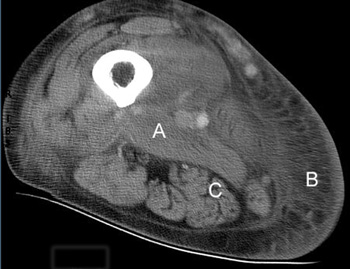

A 55-year-old woman with type 2 diabetes of 8 years' duration experienced, over 2–3 days, the onset of pain, tenderness and swelling of the medial aspect of her right thigh. She had recently commenced insulin therapy and was displaying good glycaemic control (HbA1c level of 6.4%). She had diabetic complications of autonomic and peripheral neuropathy, but no retinopathy. Other medical problems included chronic renal impairment, hypertension, polyarticular gout and hydralazine-induced lupus. A renal biopsy had not been performed, but her renal insufficiency was believed to be a result of diabetic nephropathy and hypertension. She was taking twice-daily mixed insulin (16 units in the morning and 10 units at night), felodipine (10 mg/day), paroxetine (10 mg/day), allopurinol (75 mg/day) and prednisolone (7.5 mg/day). Her serum creatinine level had peaked at 0.31 mmol/L, but stabilised at 0.21 mmol/L after cessation of an angiotensin-converting enzyme inhibitor. A 24-hour urine collection showed a creatinine clearance rate of 0.12 mL/s (normal range [NR], 1.5–2.5 mL/s) and a protein excretion rate of 4.6 g/day. Renal duplex ultrasound showed that her kidney size was well preserved, but there was a suggestion of renal artery stenosis on the right side. There was no history of recent injury or injection to her thigh. She had not experienced any rigors and was afebrile. The area of the localised, tender swelling on the medial aspect of her right thigh was not erythematous and no local lymphadenopathy was noted. Apart from the thigh swelling, there was generalised wasting and weakness of the lower limbs, loss of ankle reflexes, and loss of sensation in a stocking distribution, consistent with a diagnosis of peripheral neuropathy. Examination of her left foot revealed two small gangrenous areas. Foot pulses were present and the gangrenous areas were thought to be caused by inappropriate footwear. ![]() Figure 1: Computed tomography image of the thigh, showing marked oedema and thickening of the adductor muscle group (A), extensive subcutaneous oedema (B), and sparing of the hamstring muscle (C). |

Investigations showed an elevated white cell count of 16 x 109/L (NR, 4.0–11.0 x 109/L), a platelet count of 432 x 109/L (NR, 150–400 x 109/L), an erythrocyte sedimentation rate of 110 mm/h (NR, 7–18 mm/h) and a C-reactive protein level of 119.3 mg/L (NR, 1.6–8.7 mg/L). Creatine kinase (174 U/L; NR, < 215 U/L) and lactate (0.6 mmol/L; NR, 0.5–2.0 mmol/L) levels were normal. Separate to the swelling on the medial aspect of the thigh, a presumed thrombus was palpable in the lateral accessory long saphenous vein. A subsequent ultrasound detected this thrombus extending from the mid thigh to the lateral aspect of the knee, but no deep venous thrombosis was found. She was treated with cephalexin and aspirin. Over the next two weeks, the thigh swelling evolved into a tender, palpable mass measuring 6 x 20 cm. A computed tomography (CT) scan revealed marked swelling of the entire adductor muscle group, but no discrete mass (Figure 1). In the absence of a clear diagnosis, an exploratory operation of her right thigh was performed. This showed no haemorrhage or abscess, but evidence of extensive oedema and necrosis of the adductor muscles. Samples taken for microbiological analysis were sterile. Histological examination of a biopsy specimen showed necrotic muscle, an inflammatory cell infiltrate, fibrosis and evidence of muscle fibre regeneration. The occasional small blood vessel containing fibrin thrombus was also seen, but no features of vasculitis were identified (Figures 2 and 3). A diagnosis of diabetic muscle infarction was made. ![]() ![]() Photomicrographs (original magnification x 250) of a biopsy specimen of the adductor group of muscles. Figure 2: Longitudinal section, showing necrotic muscle fibres (A) and granulomatous tissue (B). Figure 3: Cross-section showing necrotic muscle (A), an inflammatory cell infiltrate (B) and a blood vessel containing a thrombus (C). No evidence of vasculitis was seen. |

The diagnosis of diabetic muscle infarction was made retrospectively on clinical grounds and after reviewing the subsequent investigations. The differential diagnoses — muscle strain, rupture, haematoma, myositis, infection, deep venous thrombosis, thrombophlebitis, femoral artery aneurysm, fracture or a connective tissue tumour — were excluded by the clinical presentation, together with the ultrasound, computed tomography (CT) scan and biopsy findings.

The CT scan did not reveal a discrete mass, but extensive oedema of one muscle group and sparing of an adjacent muscle group. Histologically, there was evidence of skeletal muscle fibre necrosis, with a variable amount of muscle regeneration and fibrosis. These are the typical features of diabetic muscle infarction.1 Reports of spontaneous muscle infarction appear to be virtually confined to patients with diabetes.